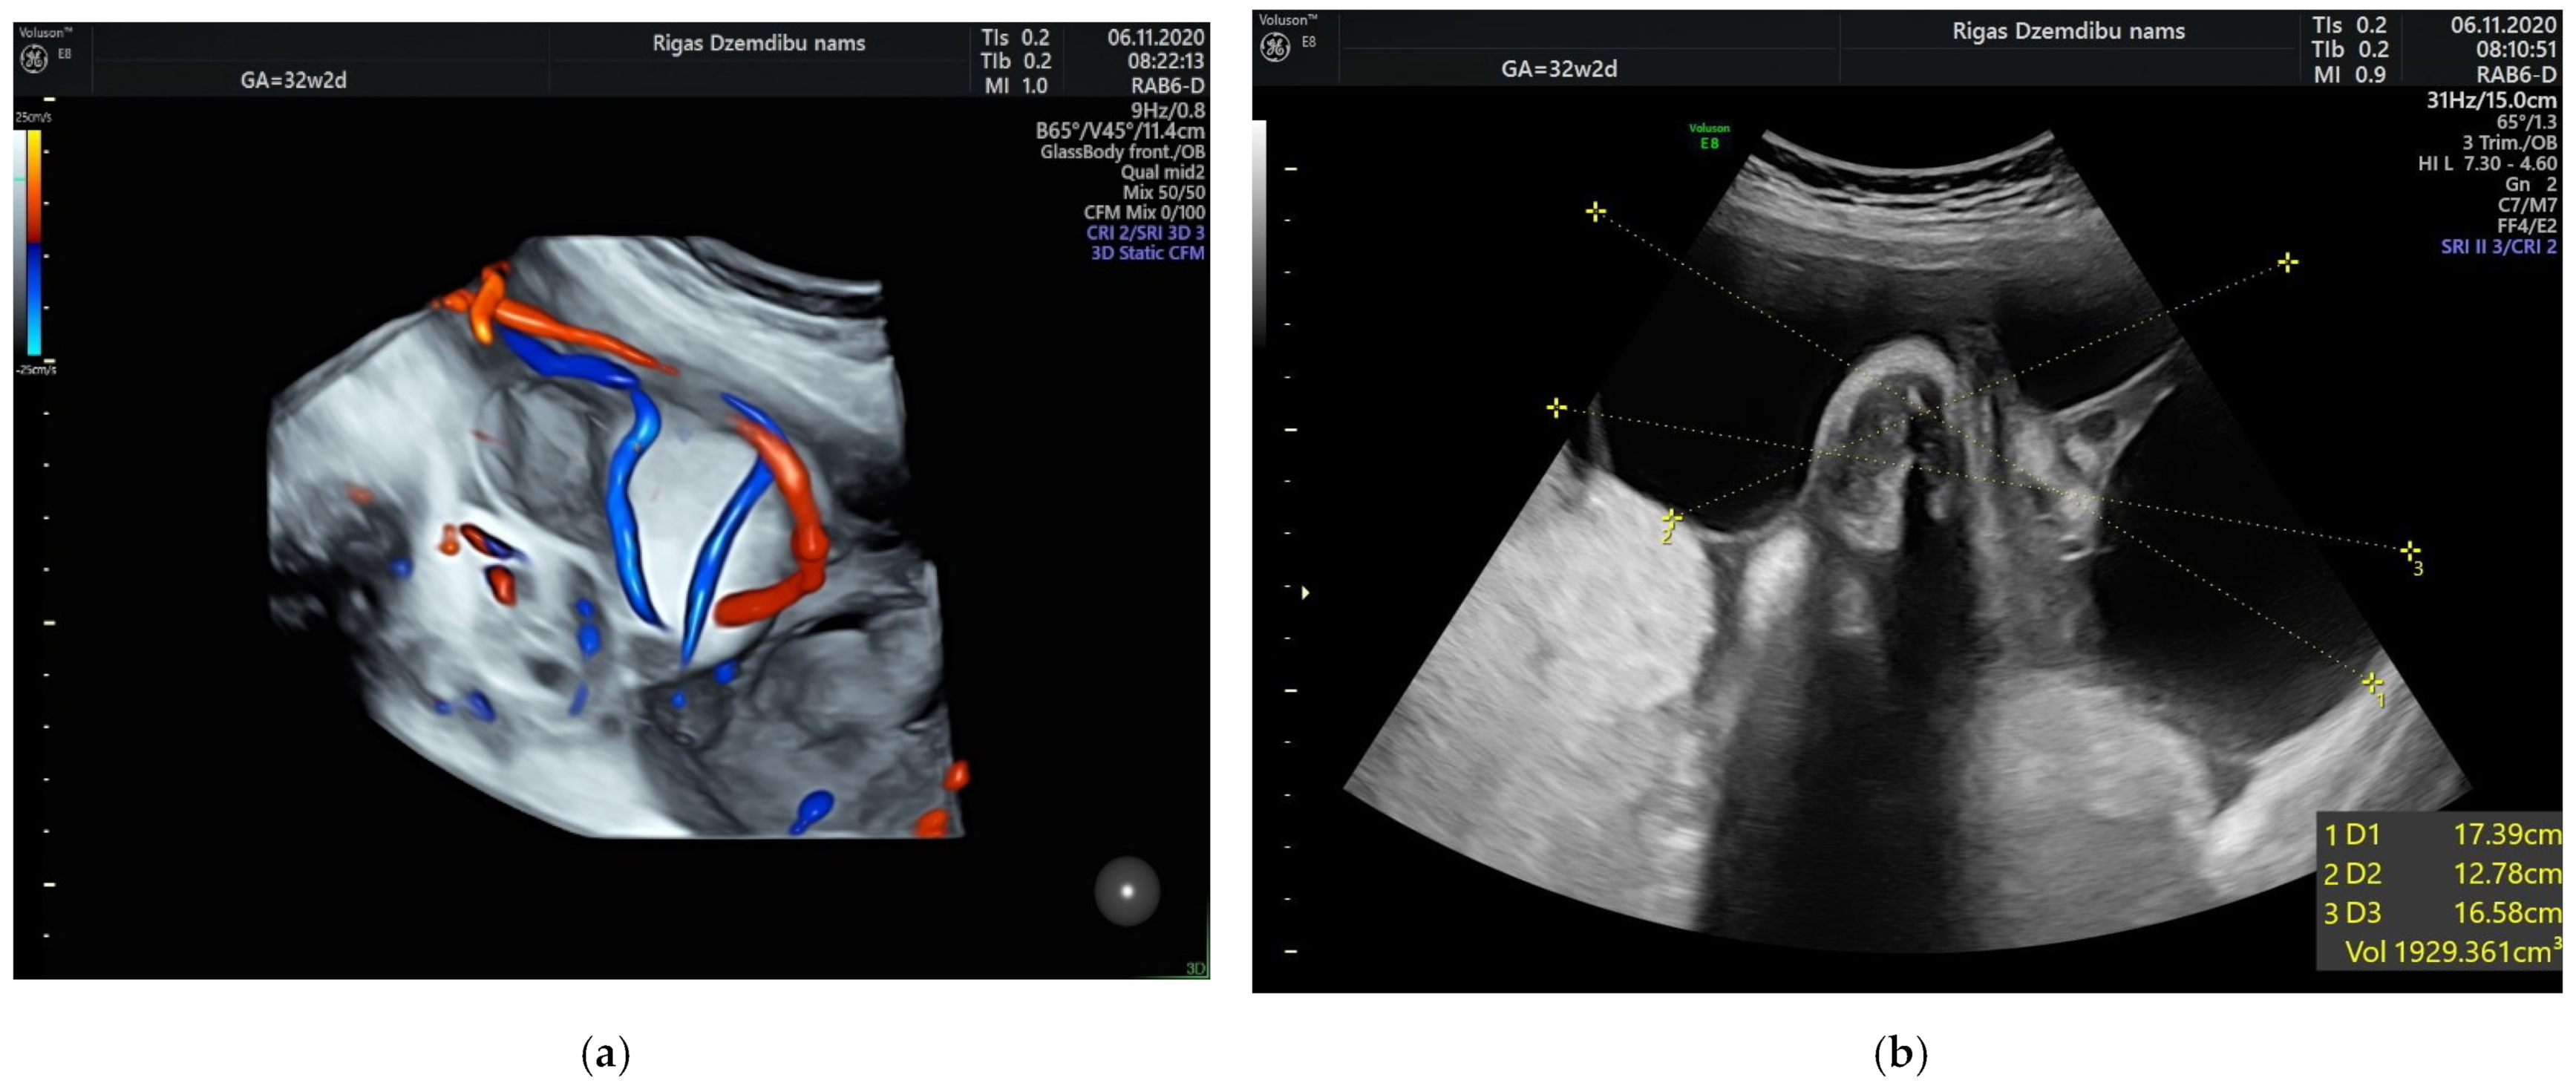

The size of the solid component was 3.4 × 2.3 cm and did not change during the pregnancy. The umbilical arteries and vein were running around and through, extra vessels were not observed in the tumor (Figure 2a). At the follow-up, the mass had rapidly enlarged in the size, from 285.32 cm3 at 26 weeks to 1929.36 cm3 at 32 weeks (Figure 2b). As well the reduction of fetal growth was observed from 30th week of gestation (Figure 3b).

Figure 3.

(a) Tumor appearance at 34 + 2 weeks; (b) Growth chart, estimated fetal weight by weeks.

At 34 weeks of gestation reduction in the size of tumor’s cystic component with freely floating superficial membranes was observed (Figure 3a). That resembles the process of rupture of the membranes without any signs of bleeding. Normal ACM PSV (49.4 cm/s) was recorded during examination of the fetus. At that time the umbilical mass decreased in size enormously and measured 120.45 cm3.

In our case the angiomyxoma was progressively growing from 24 weeks until 32 weeks. That have leaded to slowly decrease in estimated fetal weight from 50% at 24 weeks to 10% at 37 week of gestation and reduced abdominal circumference (AC) from 45% at 24 weeks to 1.1% at 34 weeks and then slightly increase in AC to 4.1% at 37 weeks. The explanation of this can be rupture and decrease in size of the angiomyxoma that have promoted better flow in umbilical vessels.